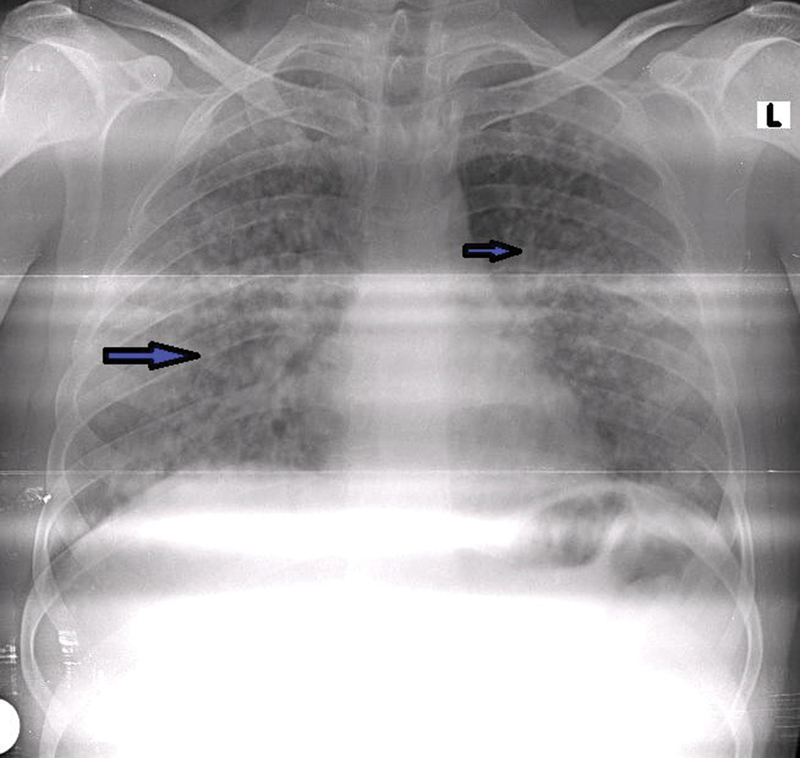

本病例报告介绍了一例中年男子,他经历了罕见和严重的水痘感染,发展为水痘肺炎和罕见的深静脉血栓形成并发症,以及随后的肺栓塞。尽管具有免疫功能,但患者的水痘感染导致了一个非典型和复杂的临床过程。患者最初表现为水疱疹、发热和疲劳,随后发展为严重缺氧和呼吸困难。影像学表现为双侧弥漫性结节实变,符合水痘肺炎。虽然水痘肺炎有很好的文献记载,但它在免疫能力强的个体中并不常见。在水痘感染的情况下,这是非常罕见的,特别是在没有免疫缺陷和没有其他危险因素的情况下,在男性患者中。该病例强调了在健康个体中保持高临床怀疑指数以及时诊断和治疗与水痘感染相关的可能危及生命的并发症的重要性。关键的学习要点包括早期识别和干预以减轻严重并发症的必要性,水痘肺炎患者可能需要血栓预防,并建议水痘肺炎患者可能需要血栓预防以预防血栓事件。

This case report presents the case of a middle-aged man who experienced a rare and severe presentation of varicella infection, with the development of varicella pneumonia and the rare complications of deep venous thrombosis, and a subsequent pulmonary embolism. Despite being immunocompetent, the patient's varicella infection resulted in an atypical and complex clinical course. The individual initially presented with a vesicopustular rash, fever, and fatigue, which progressed to severe hypoxia and dyspnea. Radiological findings revealed diffuse bilateral nodular consolidation consistent with varicella pneumonia. Although varicella pneumonia is well documented, its occurrence in immunocompetent individuals is uncommon. In the context of varicella infection, it is very rare, particularly in the absence of immunodeficiency and with no other risk factors, in a male patient. This case underscores the importance of maintaining a high index of clinical suspicion to promptly diagnose and treat potentially life-threatening complications associated with varicella infection in otherwise healthy individuals. Key learning points include the necessity of early recognition and intervention to mitigate severe complications and the potential need for thromboprophylaxis in varicella pneumonia patients and suggests the potential need for thromboprophylaxis in patients with varicella pneumonia to prevent thrombotic events.